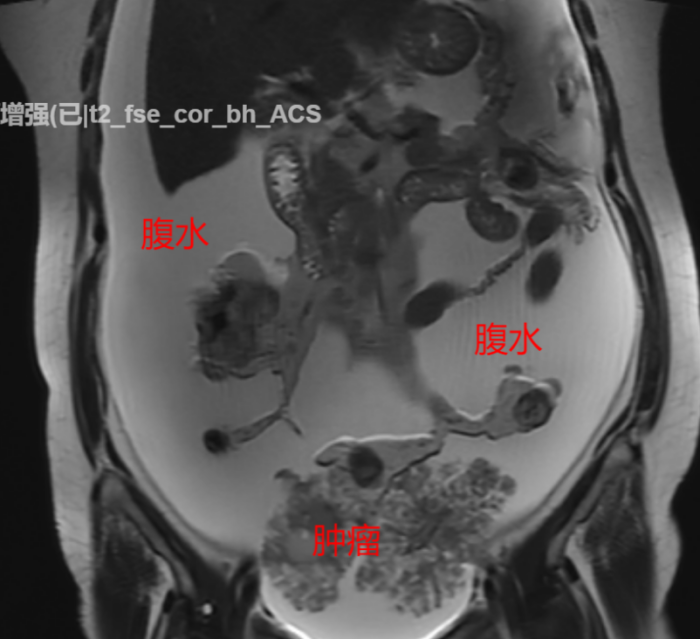

经过住院检查,医师发现何女士血清白蛋白值偏低,Ca125及HE4等卵巢癌指标异常升高。核磁共振结果进一步显示患者盆腔内有不规则团片影,其为肿瘤性病变或种植性病变的可能性较大,且患者腹腔、盆腔有大量积液,腹腔内脂肪间隙模糊,不排除外转移性病变的可能。

手术中,医疗团队成功抽出高达3000毫升的腹水,并完整切除了卵巢、输卵管、子宫以及所有盆底腹膜的多处转移病灶(包括多处膀胱及肠道浆膜层的种植病灶,较大直径为3cm),甚至精准切除了肾静脉水平的转移淋巴结,实现了对肿瘤细胞的全面“围剿”。术后,何女士在医护人员和家人的精心照料下,恢复情况良好,并顺利完成了后续化疗。